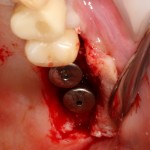

Имплантация и остеопластика: вместе или врозь? Часть II плюс Ankylos, плюс Geistlich